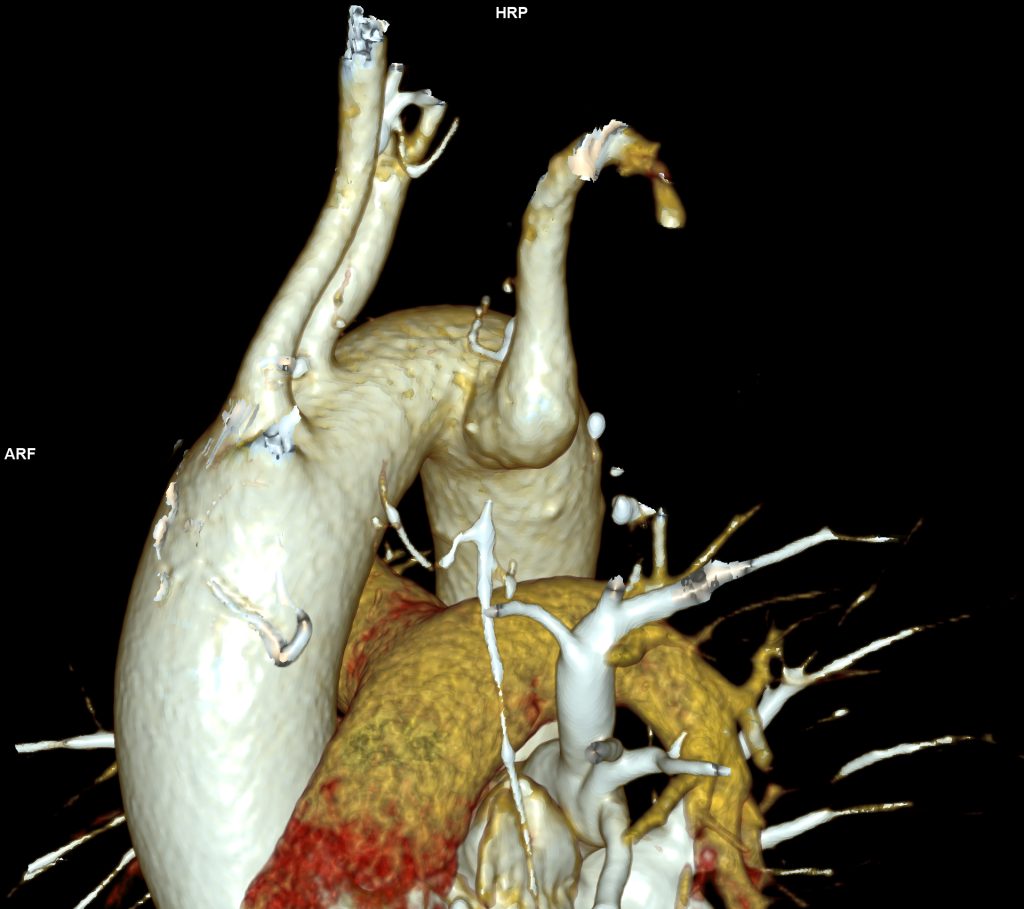

CAZ nr 57: Arc aortic de partea dreaptă si diverticul Kommerell

Figura 1: reconstrucție axială din achiziție angioCT toracică; se evidențiază arc aortic poziționat la dreapta cu originea arterei subclavii stângi dintr-o leziune cu aspect diverticular ce se dezvoltă posterior de trahee și esofag și anterior de coloana vertebrală tpracala – structura denumită diverticul Kommerell

Figura 3, 4, 5: reconstrucție de volum 3D din achiziție angioCT toracică

Discuţie caz nr 57:  pacient asimptomatic care a efectuat angioCT de aorta toracică pentru evaluarea unei creșteri de calibru a aortei la examinarea ecocardiografica. Este o anomalie de dezvoltare a arcului aortic, ce este situat la dreapta, cu originea arterei subclavii stângi dintr-o structura diverticulară.

DE LUAT ACASĂ!!! Diverticulul Kommerell este considerat a fi o eroare de dezvoltare a celui de-al patrulea arc aortic dorsal; a fost original descris la pacienții cu arc aortic la stânga ca o structura diverticulara de origine a arterei subclavii drepte aberante ce are origine din aorta după originea arterei subclavii stângi și apoi are traseu transmediastinal ajungând în fosa subclaviculară dreaptă (denumită și arteră lusoria pentru că produce la pacienți disfagie denumită disfagia lusoria).